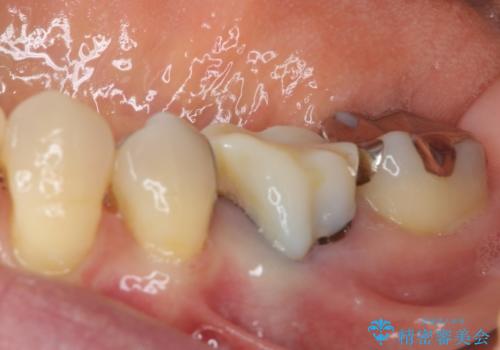

- 矯正治療を行った歯科医院で装着した前歯の仮歯が不快とのことで来院された患者様です。

仮歯自体はとても綺麗でしたが、2本の歯が欠損している部分に上唇小帯が入り込んでいたため、歯肉形成を行った上で仮歯を調整し、オールセラミックブリッジを装着することとしました。

他にも治療が必要な歯があったため、合わせてセラミッククラウンやセラミックインレーで治療することとしました。